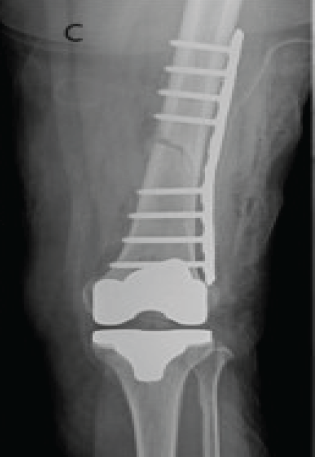

Tracking Pin Site Fractures and Measures to Overcome During Robotic-Assisted Total Knee Arthroplasty: Two Case Reports

Hyun-Min Lee , Yong-Chan Ha

………………………………p.92-96